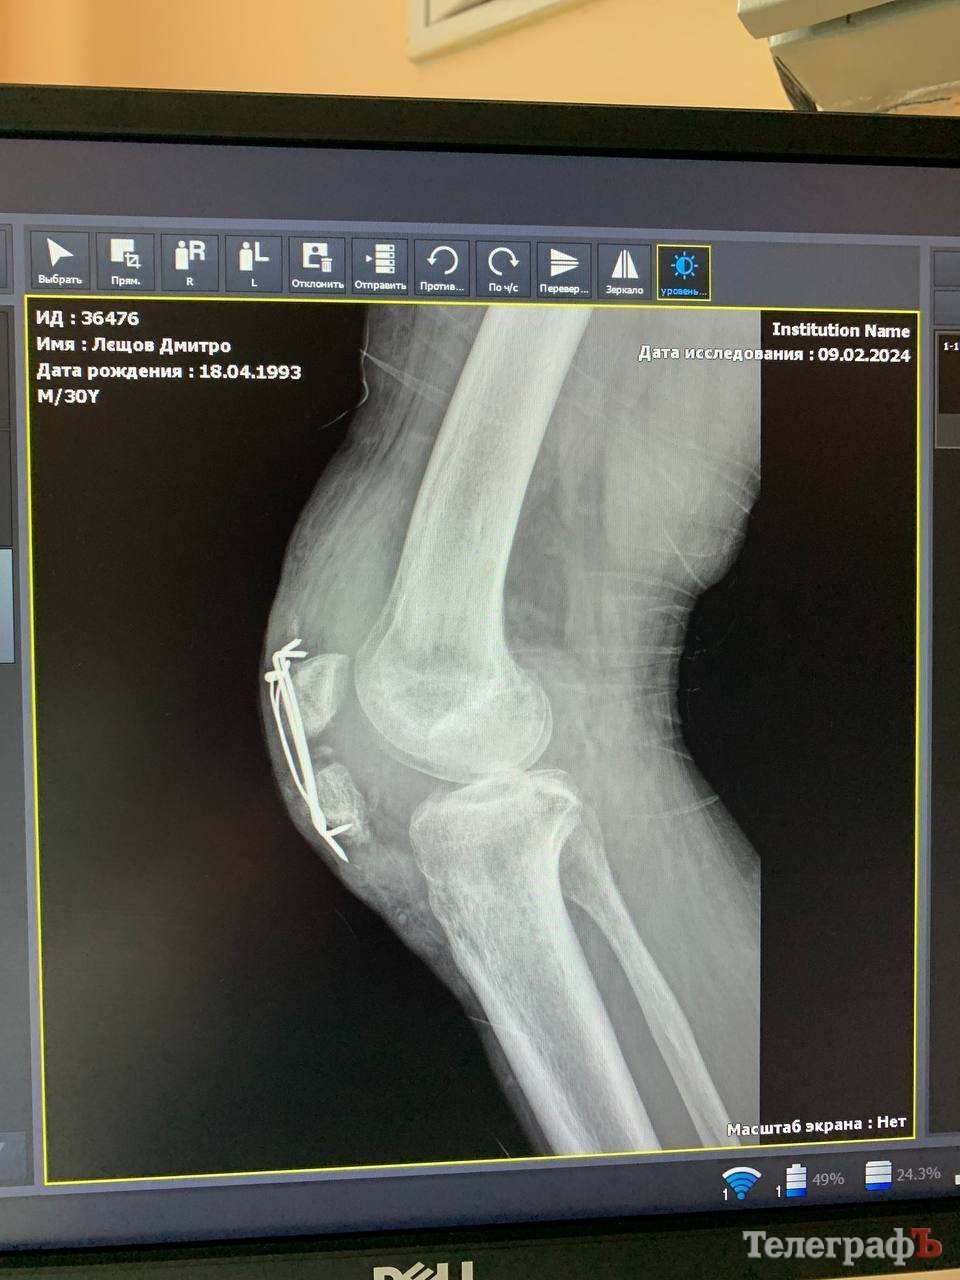

У військового була зламана рука, важкотравмований колінний суглоб, розірване коліно, серйозна травма голови.

За рік — вісім операцій, і потрібна ще одна

За цей час чоловік пройшов уже вісім оперативних втручань, і зараз йому знову потрібна операція.